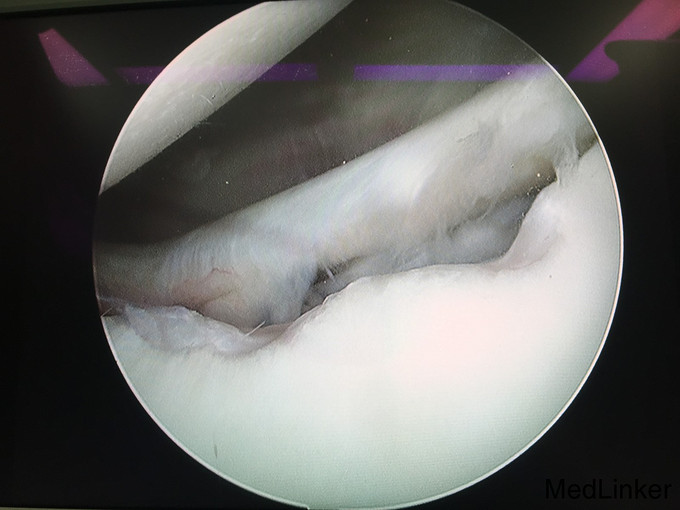

1、诊断:左肩创伤性前不稳定,左肩SLAP损伤。 2、治疗:全麻下行左肩关节镜下前盂唇、上盂唇修补术。

随访:患者术后前臂吊带悬吊5周,期间左肩被动活动。术后第6周开始左肩全方向的活动度练习及肌力练习。术后3月完全恢复左肩活动度。术后半年恢复左肩运动。 讨论:肩关节前不稳定或SLAP损伤患者,疼痛不是主要症状,关节弹响、不稳定感是主要症状。应及时前往运动医学关节外科就诊,并及时接受手术治疗。